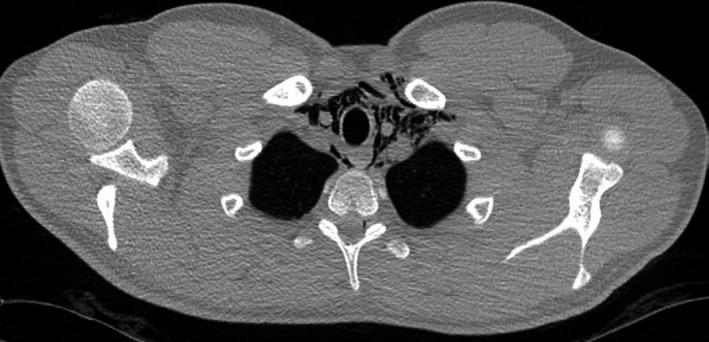

一名计划乘飞机旅行的年轻健康成年人发生自发性纵隔气肿和心包积气。

Spontaneous pneumomediastinum and pneumopericardium in a young healthy adult with plans for air travel.

Although rare, pneumomediastinum and pneumopericardium should be considered in patients presenting with sudden onset post-tussive chest discomfort.

摘要

虽然罕见,但对于出现突发咳嗽后胸部不适的患者,应考虑纵隔气肿和心包积气。